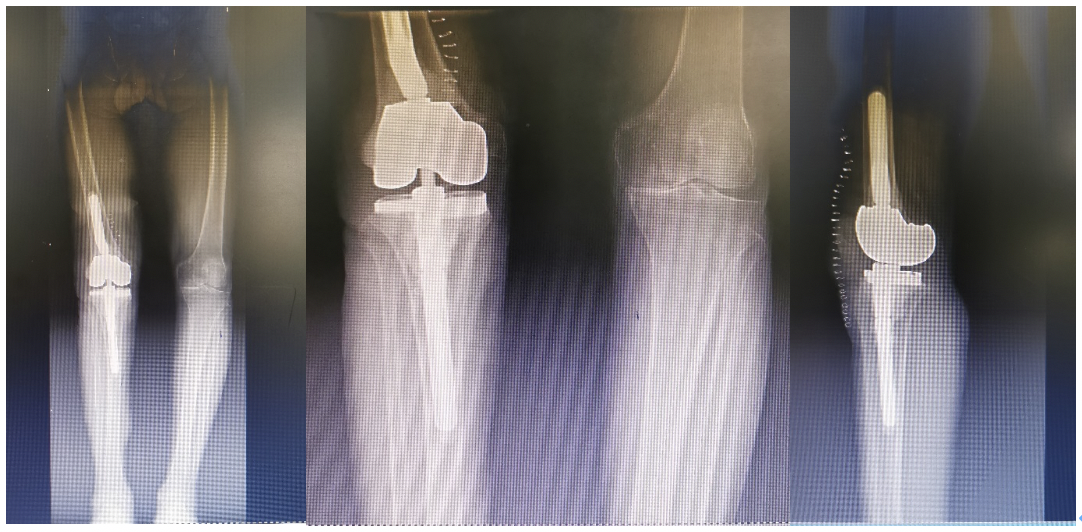

一期翻修术后影像学资料

术后影像学资料

因已行膝关节一期翻修术,患侧关节缺损较为严重,达到安德森3型(AORI III),且行二期翻修术清除抗感染填充物势必会造成进一步的缺损,严重的骨缺损和长期有效的假体固定是全膝关节翻修术最大的挑战,钽金属骨小梁(Tantalum trabecular metal)材料是捷迈邦美公司(zimmerbiomet,warsaw,Ind)公司特有的专利技术。除了拥有良好的生物相容性之外,相交于一般的骨填充材料、材质孔隙率可以达到卓越的80%,开孔率更是高达100%,在实现早期骨整合的情况下,进一步允许微血管长入,不但达到术后早期的良好康复,并且进一步大大降低了后期的再感染率。